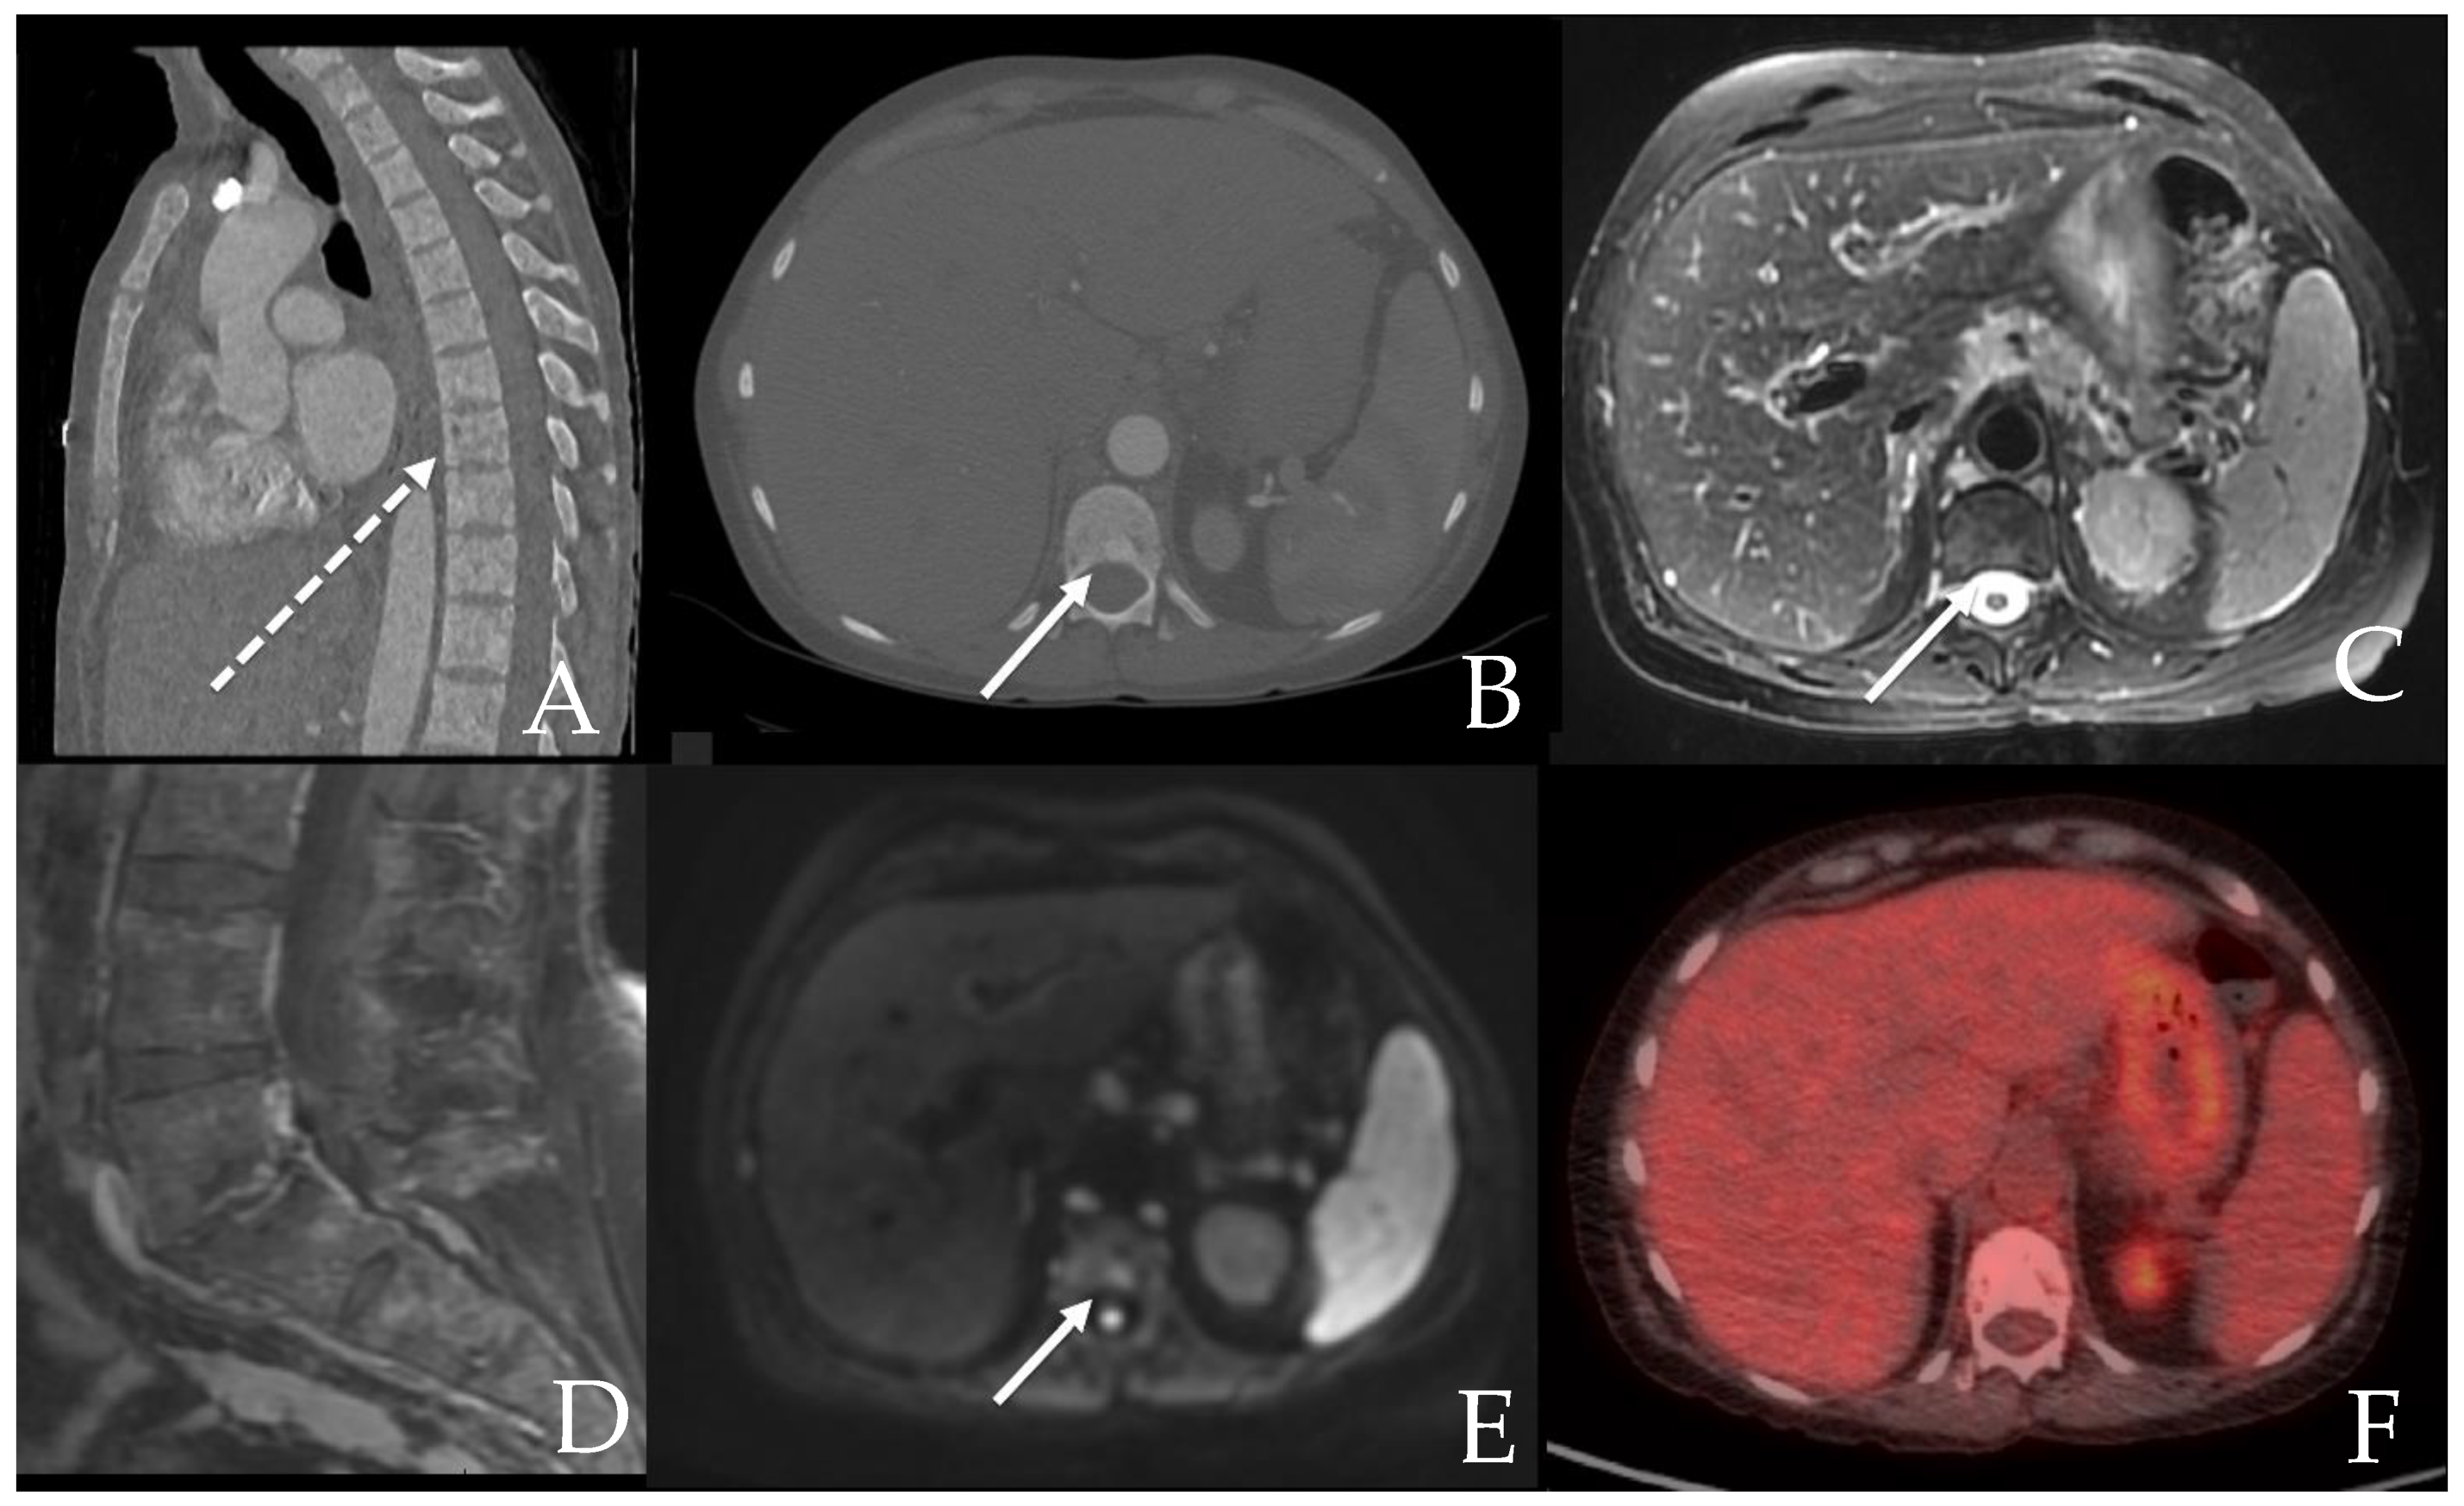

6.2. GI Tract, Liver and Spleen

6.2.2. Liver and Spleen

- Ozturk, K.; Cayci, Z.; Gotlib, J.; Akin, C.; George, T.I.; Ustun, C. Non-hematologic diagnosis of systemic mastocytosis: Collaboration of radiology and pathology. Blood Rev. 2021, 45, 100693. [Google Scholar] [CrossRef]

- Avila, N.A.; Ling, A.; Worobec, A.S.; Mican, J.A.M.; Metcalfe, D.D. Systemic mastocytosis: CT and US features of abdominal manifestations. Radiology 1997, 202, 367–372. [Google Scholar] [CrossRef] [PubMed]